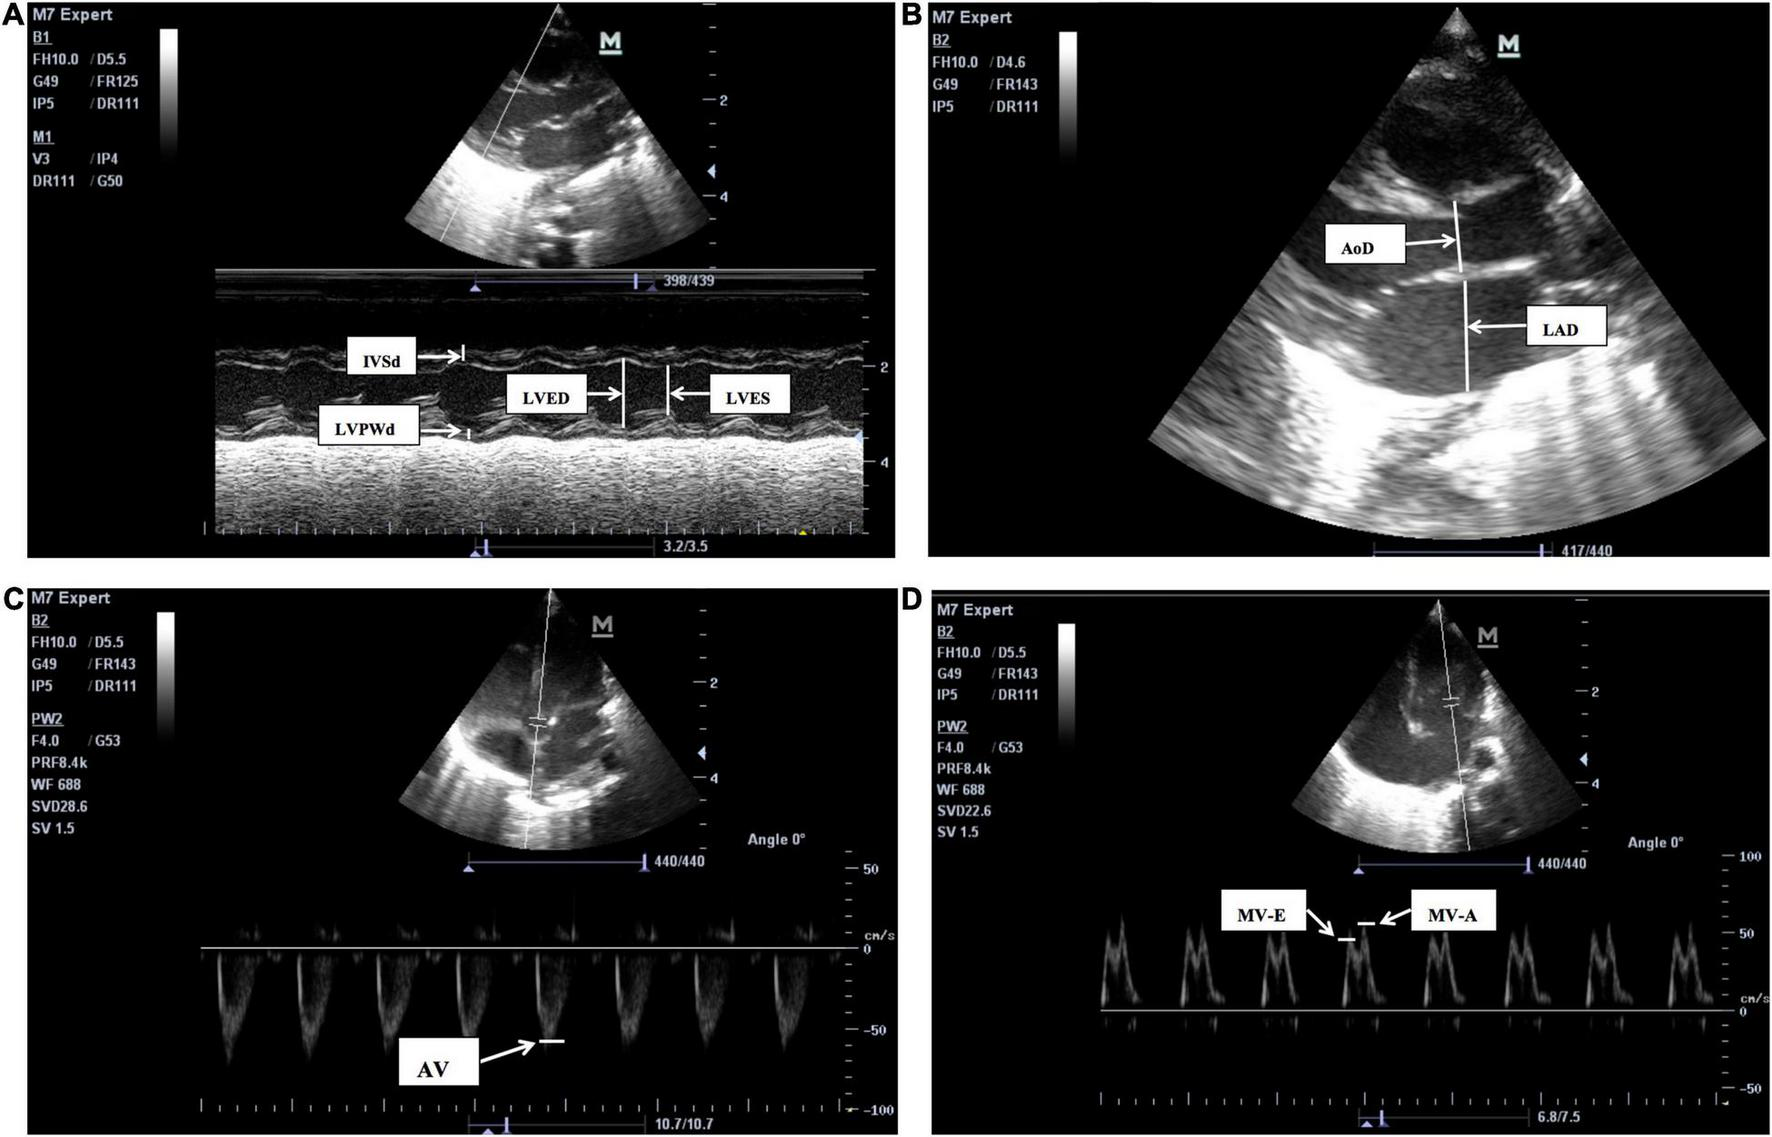

Echocardiograms were performed by a neonatologist, and examinations were completed by a neonatologist proficient in echocardiography techniques. Instant measurements were reviewed by a cardiologist. Measurements were made over three cardiac cycles, and the mean values were obtained in the standard precordial positions using the published American Child Echocardiography Guide and Standards and American NICU echocardiography Practice Guide (20, 21). The following cardiovascular measurements were obtained from parasternal long-axis views on cross-sectional LV M-mode (Figure 1): LV end-diastolic dimensions (LVED), LV end-systolic dimensions (LVES), end-diastolic interventricular septal thickness (IVSd), end diastolic LV posterior wall thickness (LVPWd), LA, and aortic root (AO) diameters, and index of LA/AO, left ventricular ejection fraction (LVEF), and left ventricular fractional shortening (LVFS). Measurements of LVED, LVES, IVSd, LVPWd, LVEF, and LVFS diameters were taken at the level of the posterior mitral valve leaflet, and measurements of the AO and LA diameters (AOD and LAD) were taken in end-systole at the level of the aortic valves. Maximum blood flow velocities were measured on the aortic and mitral valves and measured from an apical four-chamber and five chamber view using pulsed wave Doppler from a point at the center of the valves (Figure 1):aortic valve flow rate (AV), peak mitral valve flow rate E(MV-E), peak mitral valve flow rate A(MV-A), and MV-E/A. Among these traditional cardiac parameters LVED, LAD, and LA/AO represent the left heart volume load;LVFS and LVEF represent left ventricular systolic function; and MV-E and MV-E/A reflect left ventricular diastolic function. The aforementioned echocardiographic parameters, such as LAD, LA/AO, LVED, and MV-E/A have been examined as predictors of HSPDA (22, 23).

FIGURE 1

The two-dimensional (2D), M-mode or Doppler echocardiographic measurements pictures for LV structure and function. (A) The M-mode echocardiographic measurements for left ventricle and interventricular septum. IVSd, end-diastolic interventricular septum, LVPWd, left ventricular posterior wall end-diastolic thickness, LVED, Left ventricular end-diastolic, LVES, left ventricular end-systolic, LVFS, left ventricular fractional shortening, LVEF, left ventricular ejection fraction. LVFS (%), (LVED-LVES)/LVED × 100, LVEF is calculated by Teichholtz method. (B) The 2D measurements of left atrium diameters (LAD) and aortic root diameters (AoD), were taken in end-systole at the level of the aortic valves. LA/AO = LAD/AoD. (C) The pulsed wave Doppler measurements for aortic valve flow rate (AV). (D) The pulsed wave Doppler measurements for peak mitral valve flow rate E(MV-E), peak mitral valve flow rate A(MV-A), the peak mitral valve flow rate E to A (MV-E/A), MV-E/MV-A.